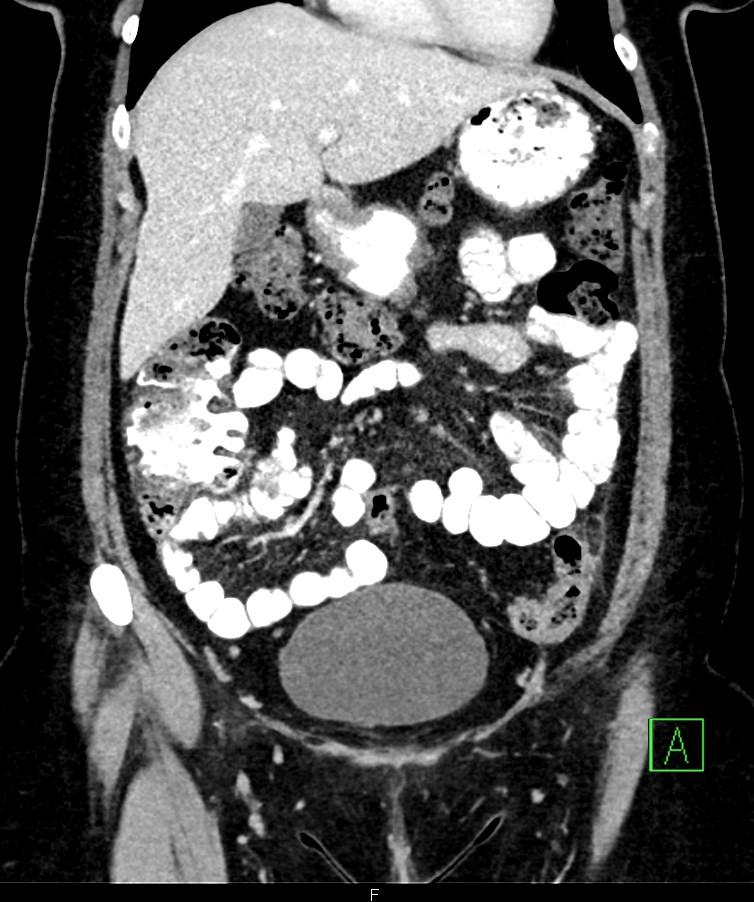

*50-year-old female present with left lower quadrant pain for 3 days.

Answer: Epiploic Appendagitis

MDCT images showed fatty density lesion adjacent to descending colon contains a characteristic hyperdense ring corresponding to thickened visceral peritoneal lining.

Epiploic appendages are small fatty peritoneal projections from the serosal surface of the colon. The inflammation of epiploic appendages can be due to torsion or venous occlusion. The disease is a self-limiting disease. Sonography and CT demonstrate an inflamed fatty lesion adjacent to the colon, including a characteristic hyperdense ring of thickened visceral peritoneal lining on CT [1].

Omental infarction has a clinical presentation similar to that of epiploic appendagitis. However, imaging illustrates an inflamed fatty mass, larger than in epiploic appendagitis and lacking a hyperdense ring on CT [1].